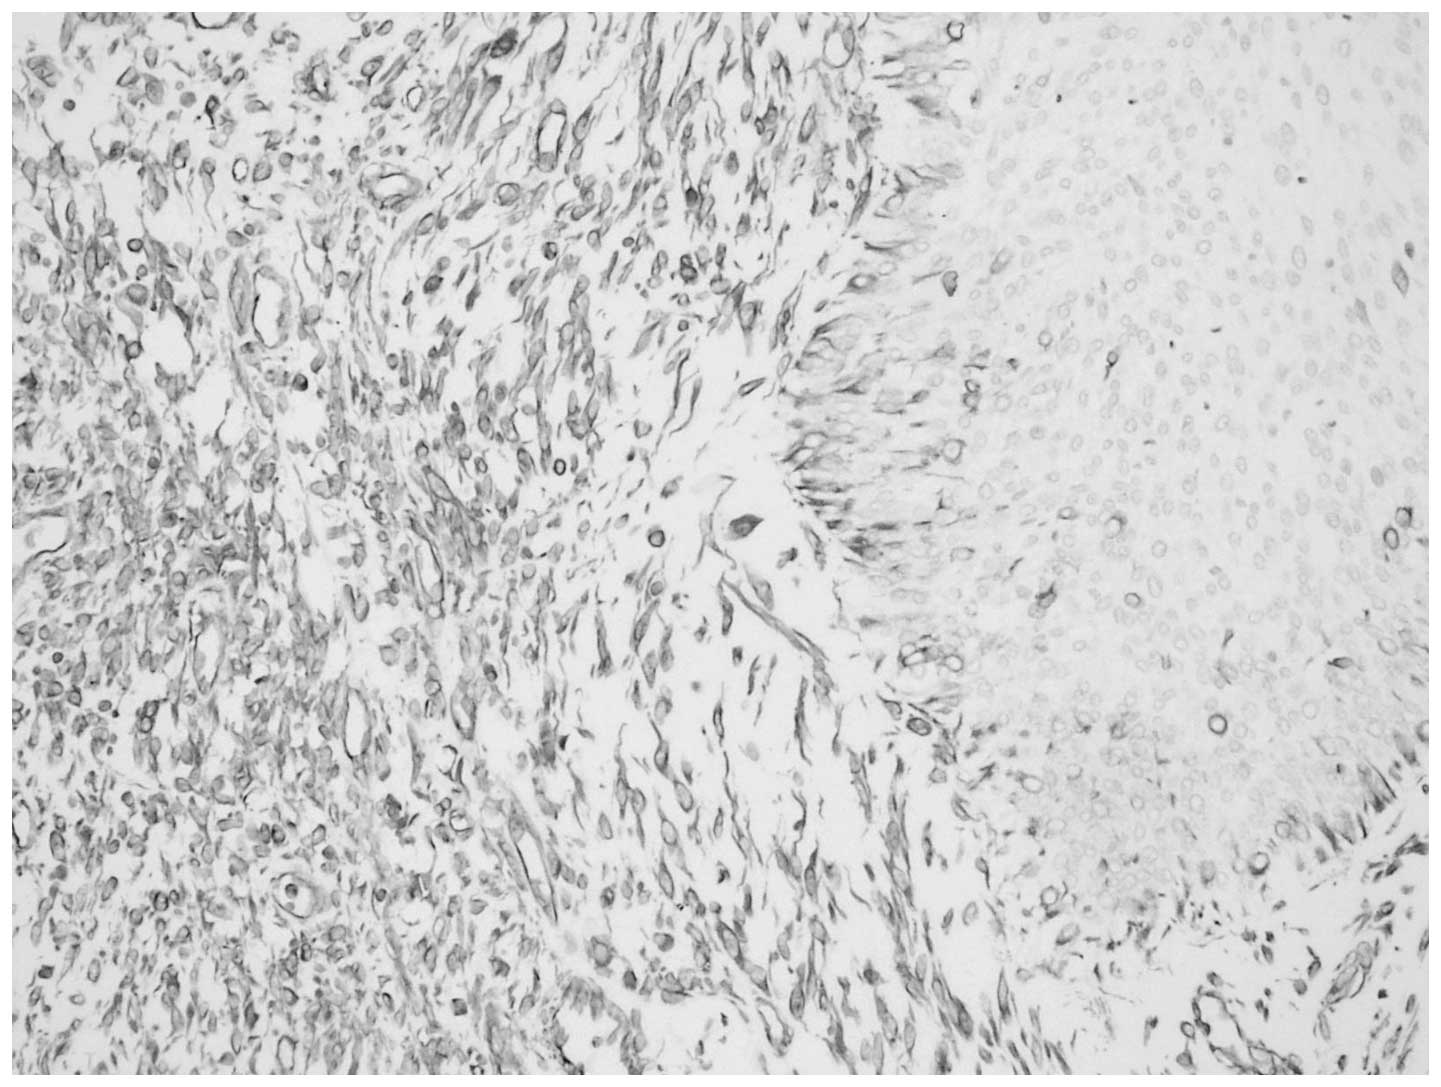

Macroscopic examination of the 13×8×6-cm nephrectomy specimen revealed a 8×5×4-cm tumoral mass in the renal pelvis. The cut section of the mass was gray-white in color, with a hard consistency. Areas of extensive necrosis were also present. The tumor had invaded the full-thickness of the renal pelvic wall and peripelvic adipose tissue. Furthermore, invasion into the renal parenchyma was observed. Histological examination of the tumor showed a malignant neoplasm comprising of epithelial and mesenchymal components, which were largely separated from each other (Fig. 2). However, in certain areas, the epithelial component blended into the sarcomatous component, generating a histological transition between the two. The sarcomatous areas primarily consisted of spindle cells, which were full of eosinophilic cytoplasm. Immunohistochemical staining was performed using a panel of markers, including cytokeratin, vimentin, Ki-67 antigen and p53. The epithelial portion of the tumor was found to stain positively for cytokeratin (Fig. 3) and the sarcomatoid spindle cells were observed to stain positively for vimentin, but negatively for cytokeratin (Fig. 4). The tumor cells in the epithelial and sarcomatous components were also found to express p53 protein in the nuclei. The expression level of p53 was >10%. Furthermore, the Ki-67 labeling indices were >20% in all of the tumor cells. Due to the advanced age of the patient, chemotherapy and radiotherapy were not administered. The patient was discharged six days after surgery and no recurrence was observed after eight months.

Figure 2

Biphasic tumor composed of an epithelial component and a mesenchmal component. Frequent mitotic figures are observable among the tumor cells. Stain, hematoxylin and eosin; magnification, ×20.